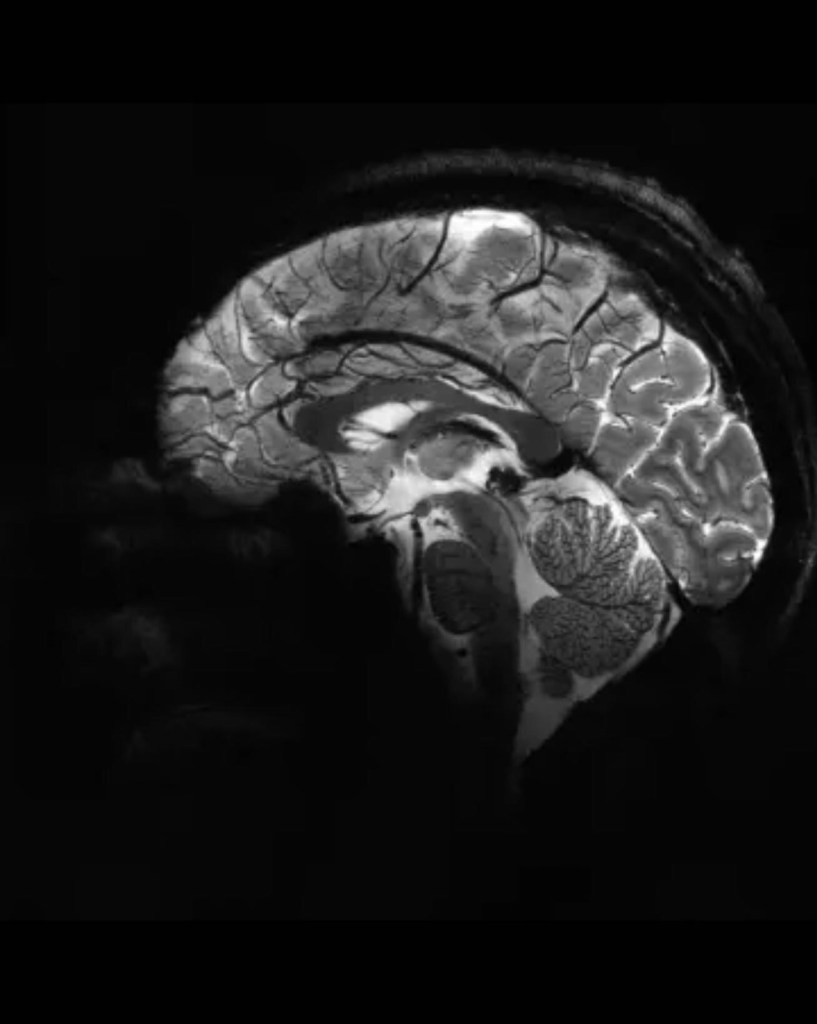

En un estreno mundial, los investigadores de la Comisión de Energía Atómica (CEA) de Francia revelaron este martes una serie de imágenes ‘in vivo’ del cerebro humano, adquiridas con la máquina de resonancia magnética más poderosa del mundo. La Iseult, que cuenta con un inigualable campo magnético de 11,7 teslas y fue construida en un esfuerzo de dos décadas, ha captado el cerebro vivo con una claridad sin precedentes.

Las más notables imágenes anatómicas del cerebro nunca antes obtenidas se tomaron en apenas cuatro minutos. Los expertos señalan que su resolución es impresionante para un lapso temporal de adquisición tan corto. Se logró una resolución en el plano de 0,2 mm y grosor de corte de 1 mm, lo que representa un volumen equivalente a unos pocos miles de neuronas.

En comparación, la misma calidad de imagen requeriría horas con los escáneres de resonancia magnética actualmente disponibles (de 1,5 o 3 teslas). Esto no es realista en la práctica, ya que los pacientes no se sentirían cómodos y cualquier movimiento haría que la imagen se vea «borrosa».